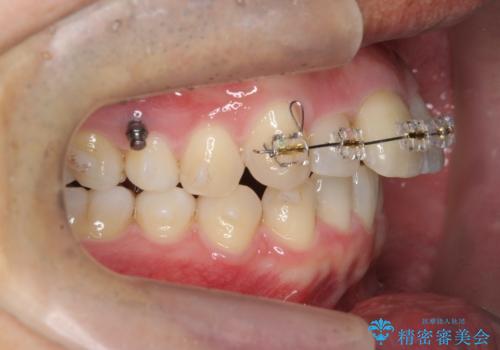

2級ディープバイト 遠心移動を伴うマウスピース矯正

・深い噛み合わせ(ディープバイト) ・2級性の咬合関係(上顎前突)・前歯のがたつき

以上のような歯並びの問題をマウスピース矯正インビザライン・カリエール・マイクロインプラント・部分ワイヤー矯正

を用いて改善していきます。

深い噛み合わせと上顎前突の状態を治すのに時間がかかりましたが、治療後は理想的で安定した咬合関係となりました。